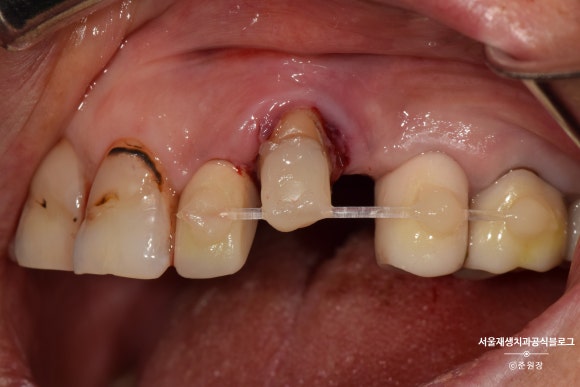

잇몸에 콕 박혀있던 요 녀석을

위 사진처럼 약~간 들어올린 상태로 고정시켰습니다.

치아가 살~짝 빠져있는 상태겠죠?

흔들리지 않겠냐고요?

약간의 생리적인 움직임만을 허용할 수 있는

레진-와이어 스플린팅을 시행합니다.

투명하고 낭창낭창한 플라스틱 와이어나 얇은 스텐와이어면 충분합니다.

인접치에 튼튼하게 고정되었습니다.

이 상태로 2주 기다려봅니다.